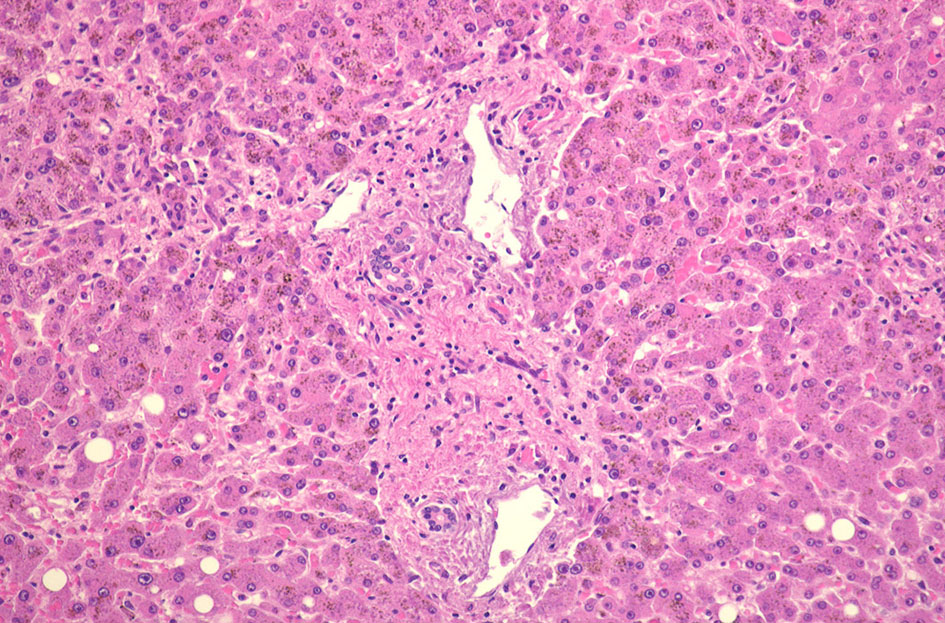

70歳代男性の骨髄。hypercellular marrow. M/E=1-2, erythropoietic hyperplasiaを認める(1, 2). megaloblastosisが出現。(3).

Mgkは成熟大型のものが多い(4). 単核, 小型球状核のMgkも認められる(5)

骨髄塗抹標本と組織(clot section)の鉄染色(クリックで大きな画像がみられます) ring sideroblastは鉄顆粒が核周囲にまとわりつくように見える赤芽球として認められる。Hb合成の乏しい幼若な大型赤芽球では認められる鉄顆粒は少ない。